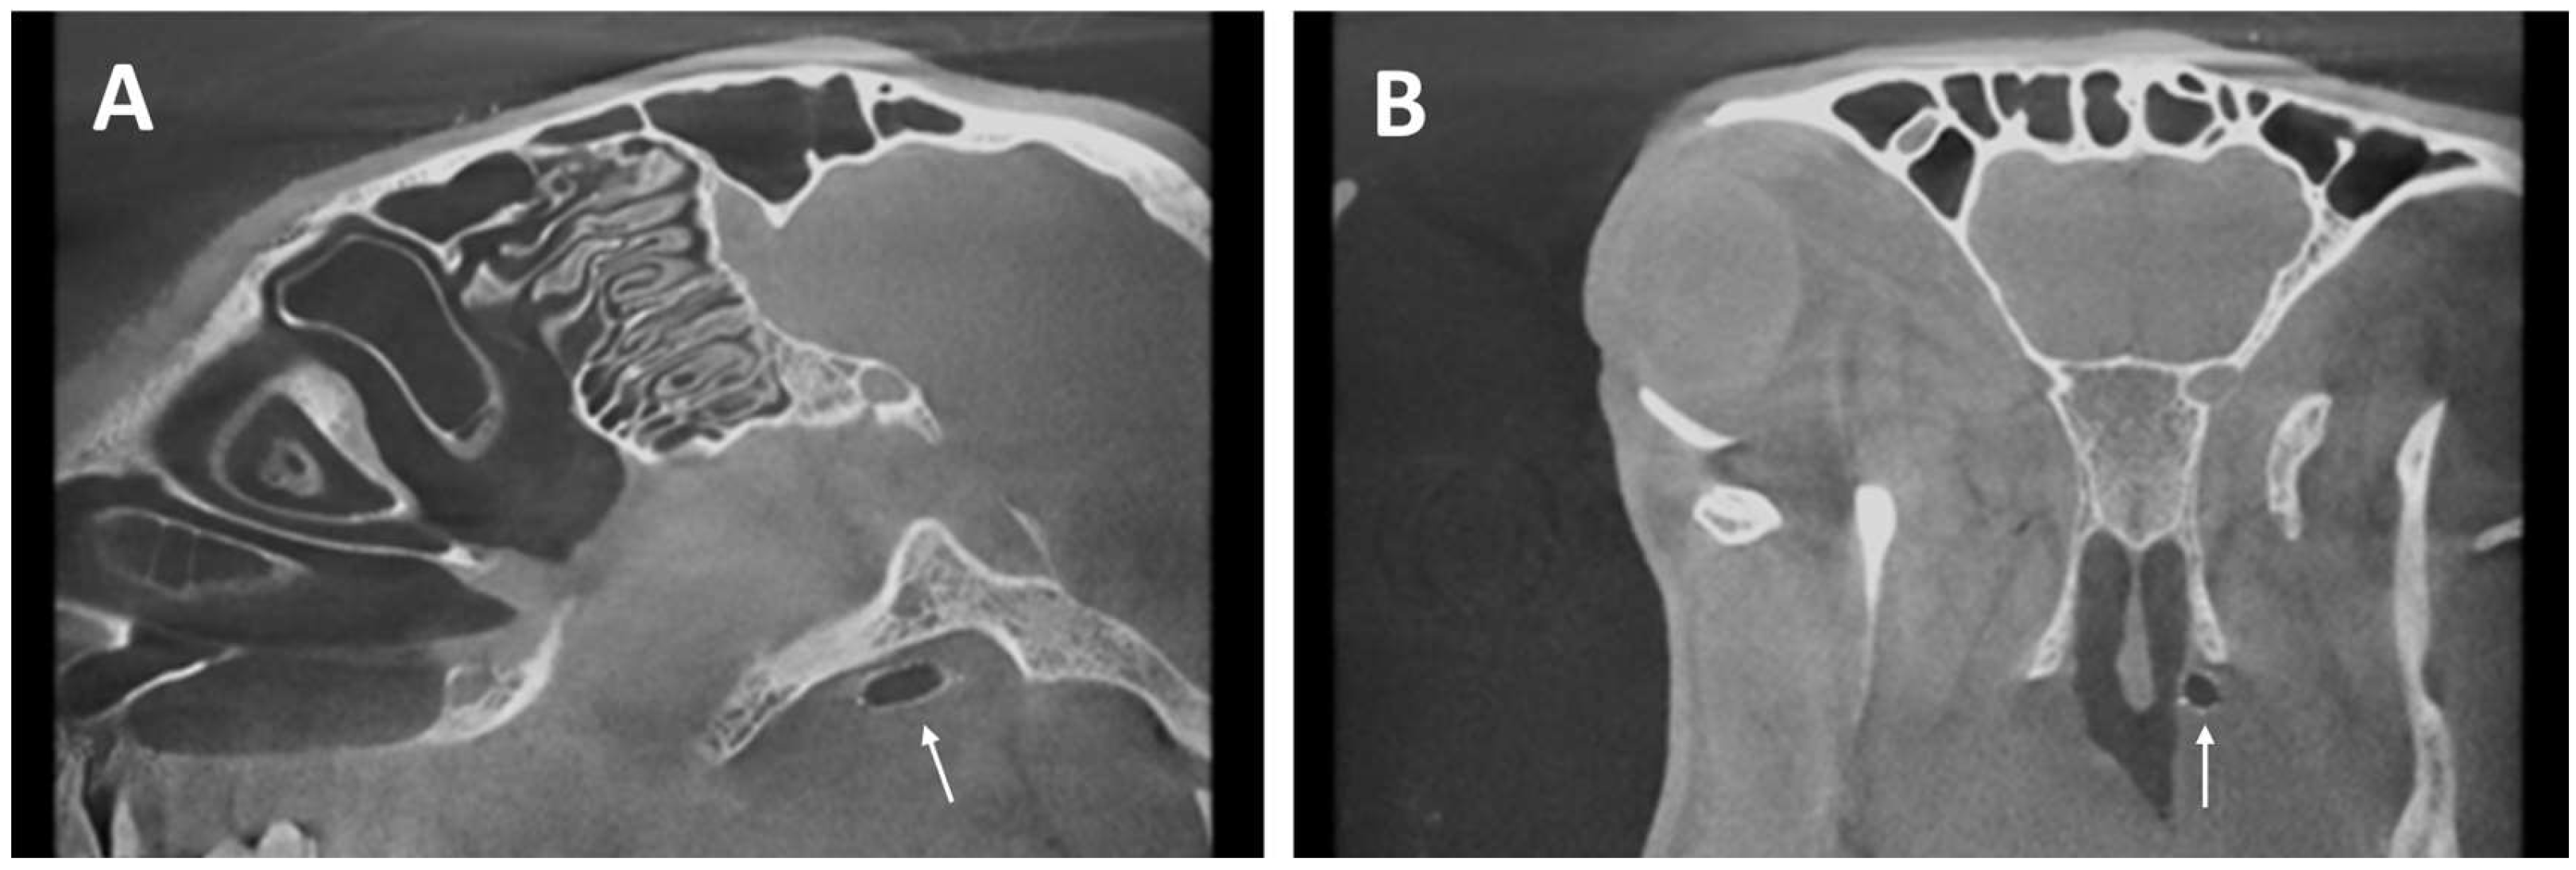

CBCT data showed that 23/24 inserted stents could be located (Figure 6) at the end of the study. However, no stent was found in 12M-3. The sheep was regularly stented (right side) and followed the study protocol as planned. In this animal, a decline of the conchae nasalis of the left nasal cavity was found in CBCT. Imaging proved that 20/24 inserted stents were found to be positioned in the ET. However, three stents (3M-4, 6M-1, and 6M-2) were not positioned as desired. The stents were found mostly in the surrounding tissue of the ET and were not directed towards the middle ear. The stent of 3M-4 was positioned orthogonal to the ET direction and the stent of 6M-1 was in the surrounding ET tissue. CBCT also revealed that the stent of 6M-2 had an abnormal, compressed shape (Figure 7B).

No stent fractures were detected in CBCT. Stent location was visually determined in relation to the individual bony anatomy of the animals based on the Proc. muscularis (Figure 7) and the channel-like bony portion of the ET [40]. All stents were located close or next to the Proc. muscularis and no stent was positioned in the bony ET part, meaning that all 20 stents in the ET were positioned as deep as anatomically possible in the cartilaginous part of the ET. However, these anatomical landmarks varied in shape and length.